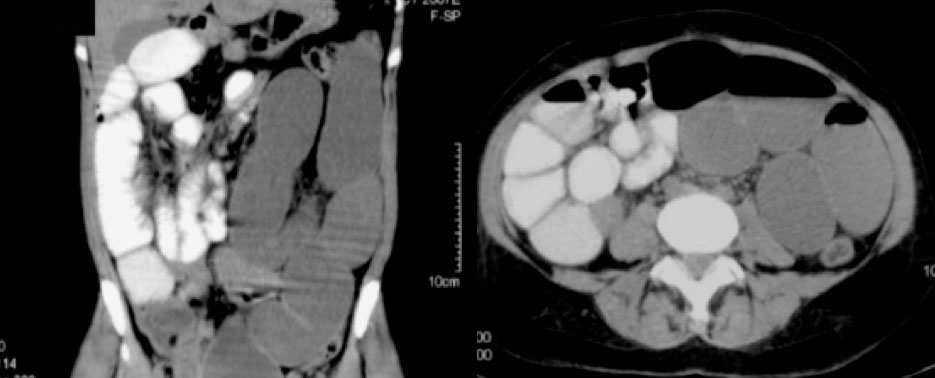

Case 11  55-year-old man with a pancreatic mass and history of recent inguinal hernia repair. Axial (A) and coronal MPR (B) CT images of the pelvis reveal:

|

Case 11  55-year-old man with a pancreatic mass and history of recent inguinal hernia repair. Axial (A) and coronal MPR (B) CT images of the pelvis reveal:

|

Retained Surgical Sponge

|

Retained Surgical Sponge  This is another example of how the sponge marker is better displayed with 3D volume rendering |